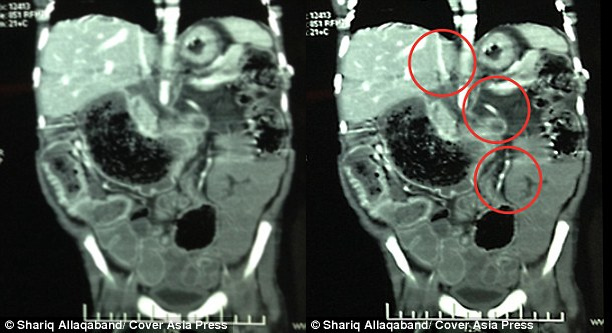

Tình trạng của Sivam chỉ được phát hiện khi cha mẹ đưa cậu bé đến Bệnh viện Tổ chức Khoa học và Y tế Ấn Độ tại New Delhi. Tiến sĩ Shilpa Sharma, trợ lý giáo sư khoa nhi tại đây đã nhận thấy sự khác lạ của Sivam. Bà quyết định đưa cậu bé đi chụp X-quang ngay lập tức và kinh ngạc phát hiện vật thể lạ là một búi tóc dài tới 1,22 mét trong dạ dày Sivam.

Tiến sĩ Sharma cho biết: "Có rất ít khí ở vùng bụng. Búi tóc đã lan khắp dạ dày và len lỏi cả vào ruột cậu bé. Chúng tôi đã phải tiến hành phẫu thuật và lấy ra được một búi tóc có hình dạng gần như trùng khớp với hình dạng bên trong dạ dày".

| Phim X-quang cho thấy hình ảnh búi tóc chiếm hầu hết dạ dày và lan cả xuống ruột. (Ảnh: Cover Asia Press) |